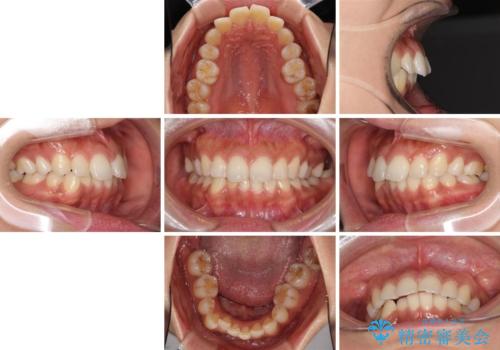

抜歯矯正の後戻り インビザラインによる再矯正治療

- 以前矯正治療をされていましたが、後戻りが起きたことを気にして来院された患者様です。

全顎的に認められた叢生を改善するため、インビザラインにて治療を行うこととしました。

前歯の叢生の改善を目的として、IPR(歯と歯の間を削る)と歯列全体の後方移動によって歯並びを整えることとしました。

毎日22時間の装着時間を守ってくださいましたが、ハイペースにマウスピースを交換することなく、慎重に治療を進めてくださったので、治療期間はやや長くなりました。

臼歯部も含め、叢生が綺麗に改善され、患者様には大変満足していただきました。